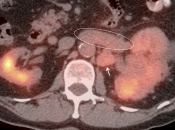

- FDG is excreted and accumulates in the kidney, easily masking areas of pathologic uptake.

- Nearly every PET/CT scan is performed without intravenous contrast, markedly limiting evaluation of the kidneys on the CT portion of the exam.

Primary Lesion: Because many primary RCCA lesions are only mildly FDG avid, we must raise a suspicion of RCCA for any FDG-avid renal lesion (cystic or solid) — unless we can clearly characterize it as a fat-containing angiomyelolipoma.

Metastatic Disease: Metastatic RCCA lesions are usually more FDG avid than the primary lesion (nearly all demonstrate metabolic activity greater than liver uptake).

- Direct invasion of adjacent structures.

- Tumor thrombus into renal vein must be excluded.

- Hematogenous spread, often to lungs, bone, liver, and brain.

- Lymphatic spread to regional and distant lymph nodes.